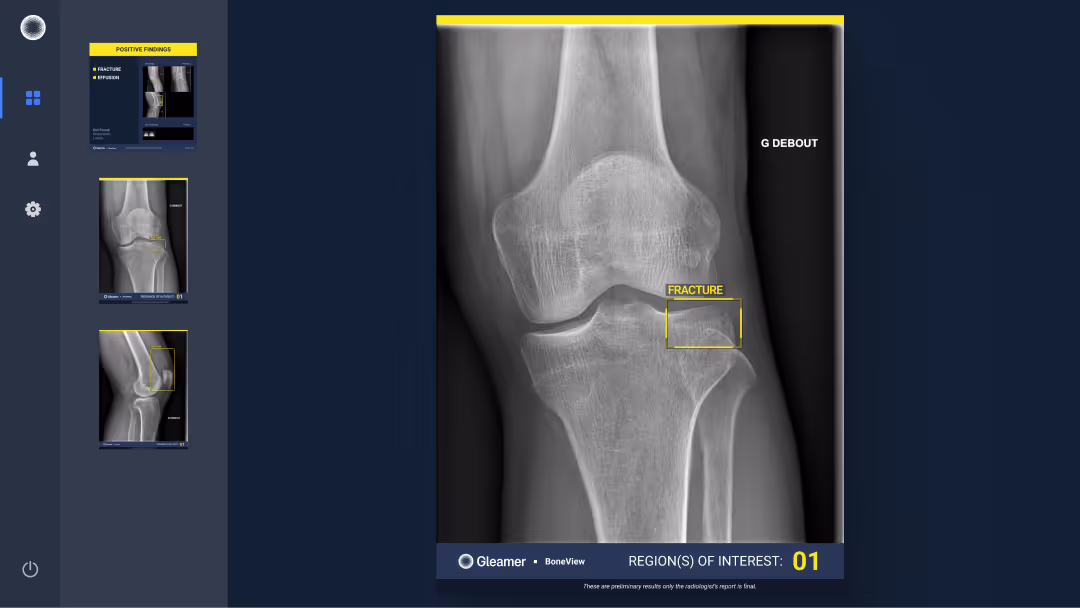

A 63-year-old male with lingering pain after a trail run.

Results

BoneView detected a fracture of the lateral tibial plateau and associated effusion. The fracture has a high risk of displacement.